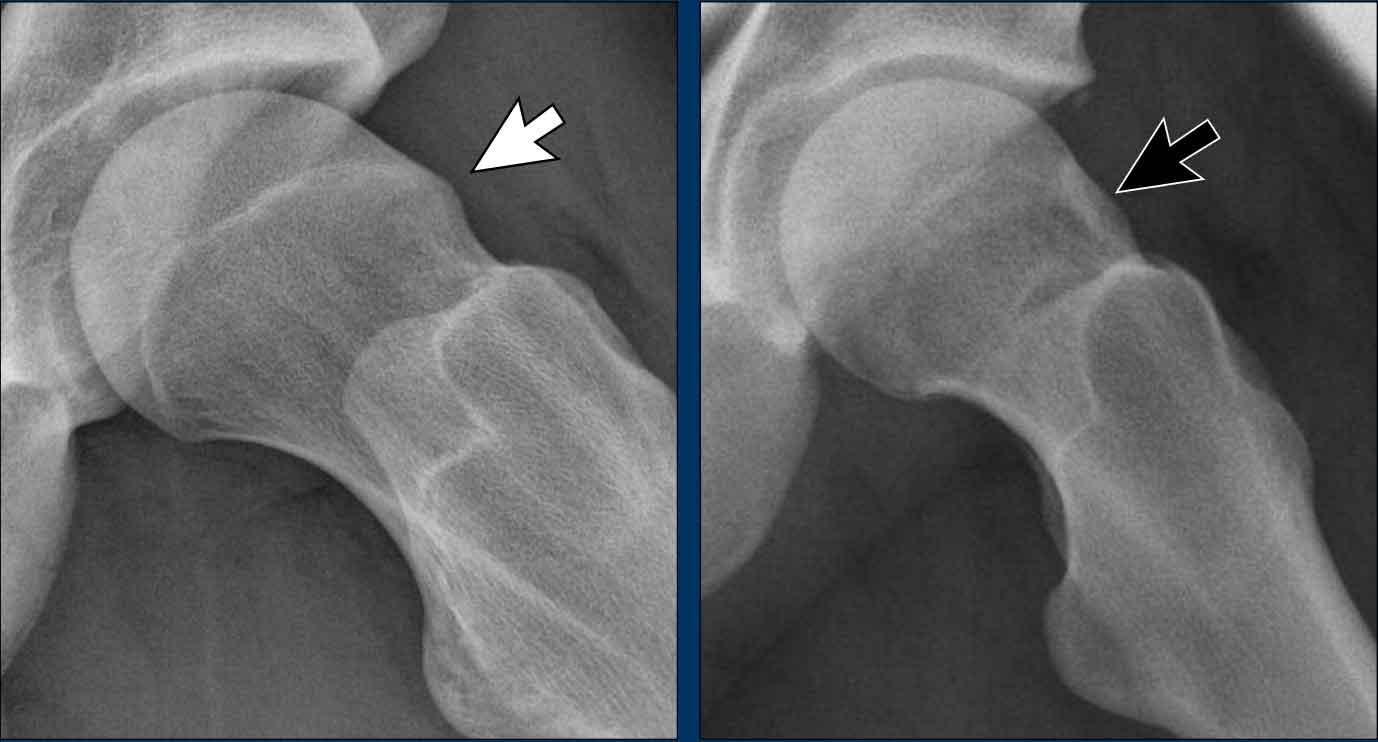

AP and Dunn view

Tư thế Dunn

Tư thế Dunn là tư thế chụp nghiêng giúp hiển thị rõ vùng tiếp nối chỏm-cổ xương đùi theo góc độ thường không thấy được trên các tư thế tiêu chuẩn như tư thế thẳng trước-sau (AP) hoặc tư thế nghiêng. Tư thế này được thực hiện bằng cách cho bệnh nhân nằm ngửa với háng bên tổn thương gấp khoảng 45° và dạng 20° đến 30° ở tư thế xoay trung tính.

Tư thế này cho phép quan sát rõ hơn mặt trên-trước của vùng tiếp nối chỏm-cổ xương đùi, vốn thường khó đánh giá trên các tư thế tiêu chuẩn và là vị trí hay gặp nhất của biến dạng dạng cam.

Hình ảnh

Vận động viên thể dục dụng cụ 20 tuổi với các triệu chứng ở hông.

Trên phim chụp AP, vùng đầu-cổ xương đùi trông bình thường.

Trên phim chụp tư thế Dunn, có hình thái Cam ở cả hai bên (mũi tên).